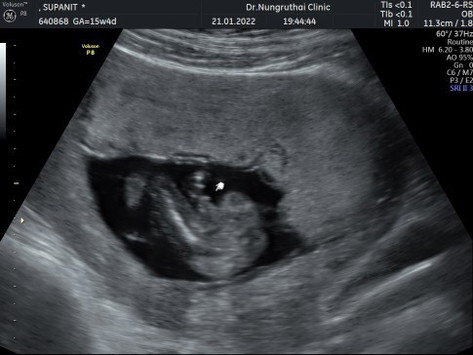

15week แบบนี้เพศชายจริงไหมคะเเม่ๆ

ภาพซาวด์ตอน 15weekค่ะ ภาพเเรกเน้นดูเพศ ผญ หรือ ผช คะเเบบนี้ เเต่คุณหมอบอก ผช #15week

ของเราดูรูปบนนะมีชี้ออกมาเป็นเด็กชายคับ

มีชี้ๆ ออกมา น่าจะชายนะคะ😁

ผลดาวส์ซินโดรมออกมาเเล้วค่ะ รู้เพศด้วย เพศชายจริงๆค่ะ 🎉🎉